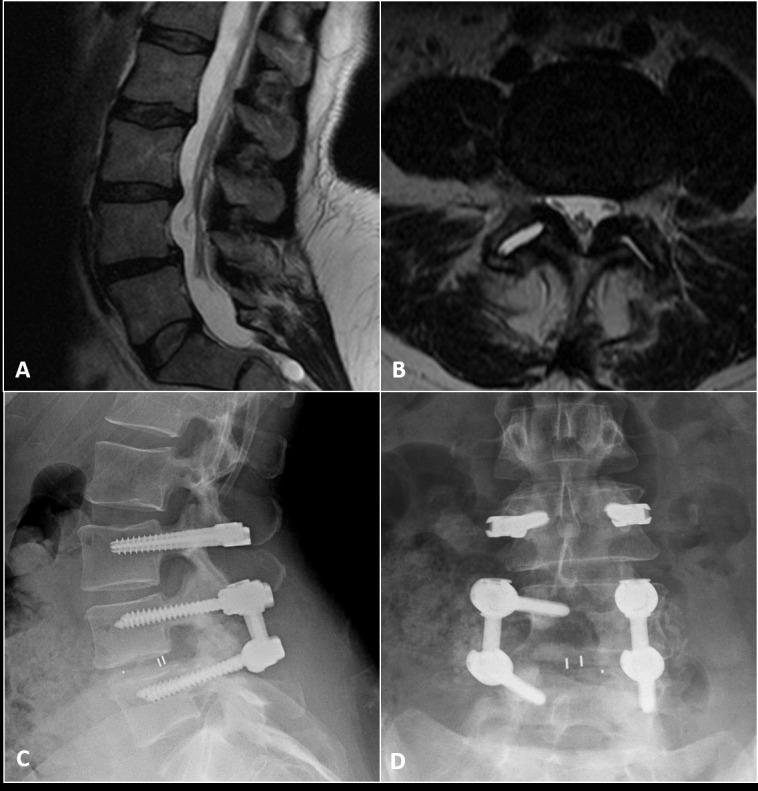

A clinical cohort investigation was conducted of 66 consecutive patients (31 female, 35 male; mean age: 53 years, range: 25 - 76 years) who underwent posterior lumbar instrumentation with the Dynesys Transition Optima (DTO) implant (Zimmer-Biomet Spine, Warsaw, IN) hybrid dynamic stabilization and fusion system over a 10-year period. The median length of follow-up was five years. DTO consists of pedicle screw fixation coupled to a rigid rod as well as a flexible longitudinal connecting system. All patients had symptoms of back pain and neurogenic claudication refractory to non-surgical treatment. Patients underwent lumbar arthrodesis surgery in which the hybrid system was used for stabilization instead of arthrodesis of the stenotic adjacent level.

Indications for DTO instrumentation were primary degenerative disc disease (n = 52) and failed back surgery syndrome (n = 14). The most common dynamically stabilized and fused segments were L3-L4 (n = 37) and L5-S1 (n = 33), respectively. Thirty-eight patients (56%) underwent decompression at the dynamically stabilized level, and 57 patients (86%) had an interbody device placed at the level of arthrodesis. Complications during the follow-up period included a single case of screw breakage and a single case of pseudoarthrosis. Ten patients (15%) subsequently underwent conversion of the dynamic stabilization portion of their DTO instrumentation to rigid spinal arthrodesis.

对连续66例患者(31例女性,35例男性;平均年龄:53岁,范围:25 - 76岁)进行了一项临床队列研究,这些患者在10年期间接受了使用Dynesys Transition Optima(DTO)植入物(捷迈邦美脊柱公司,印第安纳州华沙)混合动态稳定与融合系统的后路腰椎内固定术。随访时间中位数为5年。DTO包括与刚性杆相连的椎弓根螺钉固定以及柔性纵向连接系统。所有患者均有背痛和神经源性间歇性跛行症状,非手术治疗无效。患者接受了腰椎融合手术,其中使用混合系统进行稳定,而非对狭窄的相邻节段进行融合。

DTO内固定的适应证为原发性椎间盘退变(n = 52)和腰椎手术失败综合征(n = 14)。最常进行动态稳定和融合的节段分别是L3 - L4(n = 37)和L5 - S1(n = 33)。38例患者(56%)在动态稳定节段进行了减压,57例患者(86%)在融合节段植入了椎间融合器。随访期间的并发症包括1例螺钉断裂和1例假关节形成。10例患者(15%)随后将其DTO内固定的动态稳定部分转换为刚性脊柱融合术。